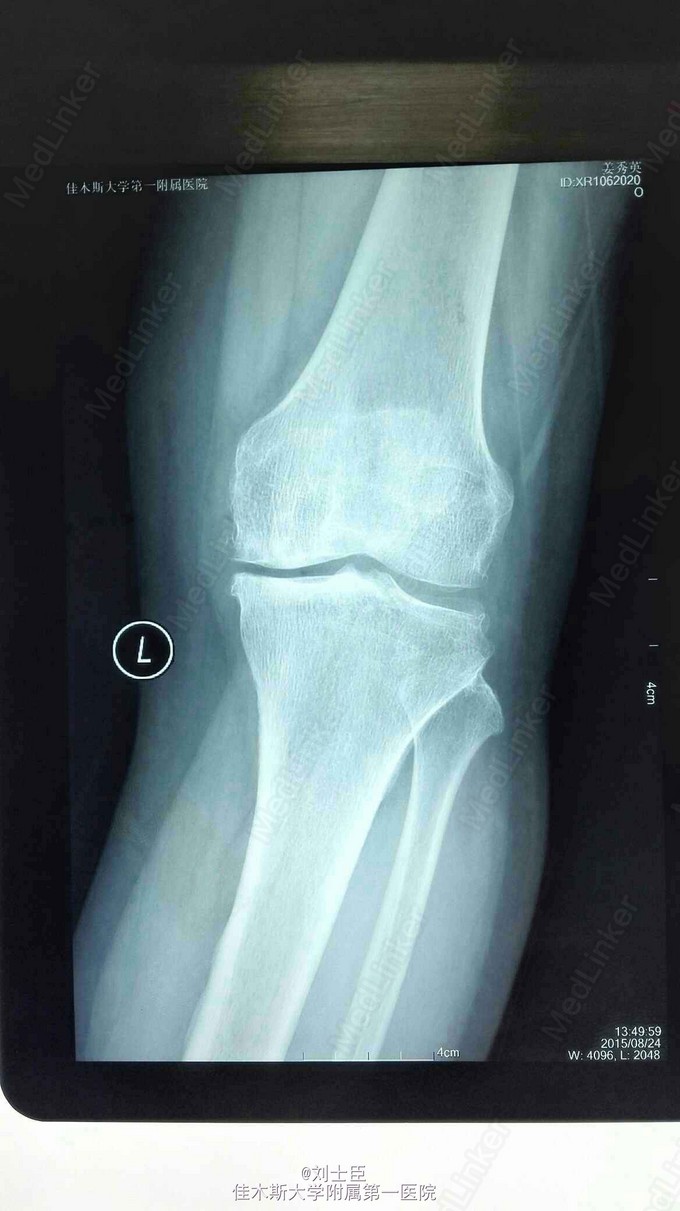

xx,女,54岁。左膝疼痛伴活动受限5年加重1个月。上下楼困难,走平路500米跛行。

左膝内侧压痛明显,伸直10度,屈曲100度。蹲起困难。过伸过曲实验阳性。

左膝关节骨性关节炎。 膝关节镜清理术加腓骨截骨术。